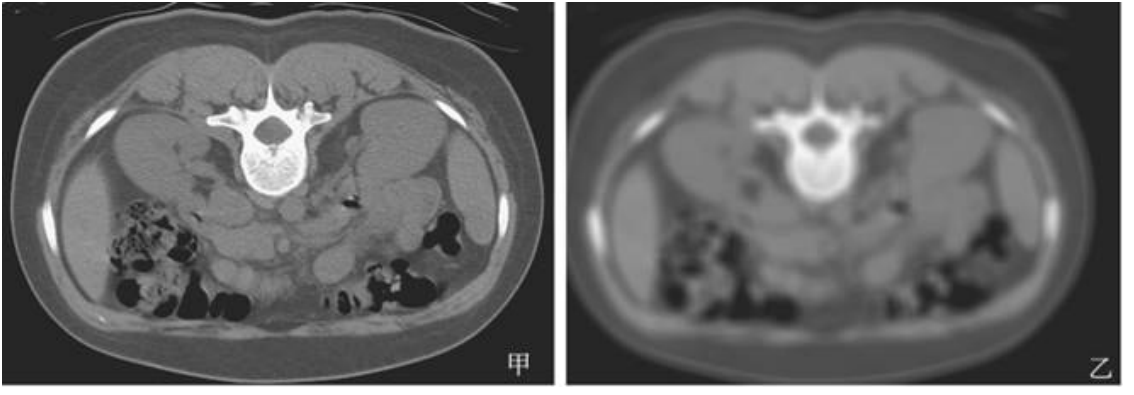

25.附圖中,甲為原始影像,影像乙與影像丙最有可能為何種影像濾波處理後的結果?

(A)影像乙為高通(high-pass)濾波而影像丙為低通(low-pass)濾波 (B)影像乙為低通(low-pass)濾波而影像丙為高通(high-pass)濾波 (C)二者皆為高通(high-pass)濾波但使用不同之kernel (D)二者皆為低通(low-pass)濾波但使用不同之kernel